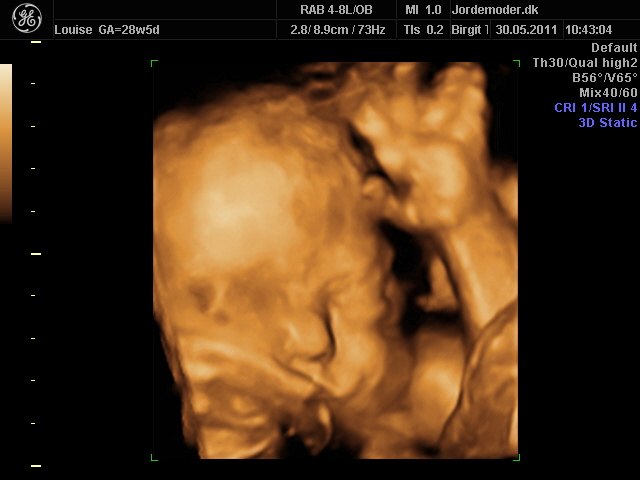

Så kom vi til 3d scanning igår. Lillepigen er slet ikke så stor som egen Jm kønnede hende HELDIGVIS! 1500 gram ca vejer hun nu, 28+6....

Hun har den fineste mund, jeg er helt misundelig på de smukker læber hun har.¨Ja hun er jo alt i alt bare dejlig, og jeg har ikke engang set hende sådan helt rigtig endnu.... Også har hun nogen gode runde kinder....

I skal ikke snydes for billeder af vores lille skønhed...